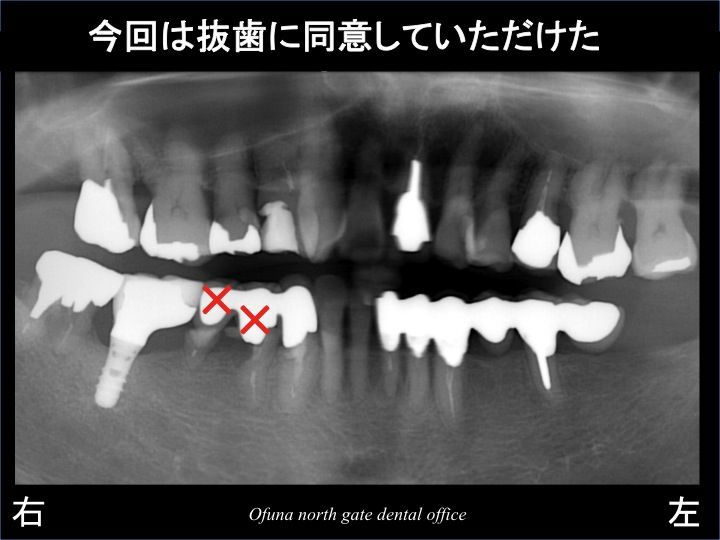

ダメになった部分を拡大してみましょう!

見る人が見れば明らかに分かるような 悪い状態です。

その結果、ようやく抜歯に同意していただけました。

次に問題となったのが、抜歯後の治療の進め方です。

2歯とも抜歯してしまうと 当然のことながら 欠損してしまいます。

患者様は、治療期間中に歯がないことは嫌とのことでした。

また、義歯(入れ歯)を使用することもご希望されませんでした。